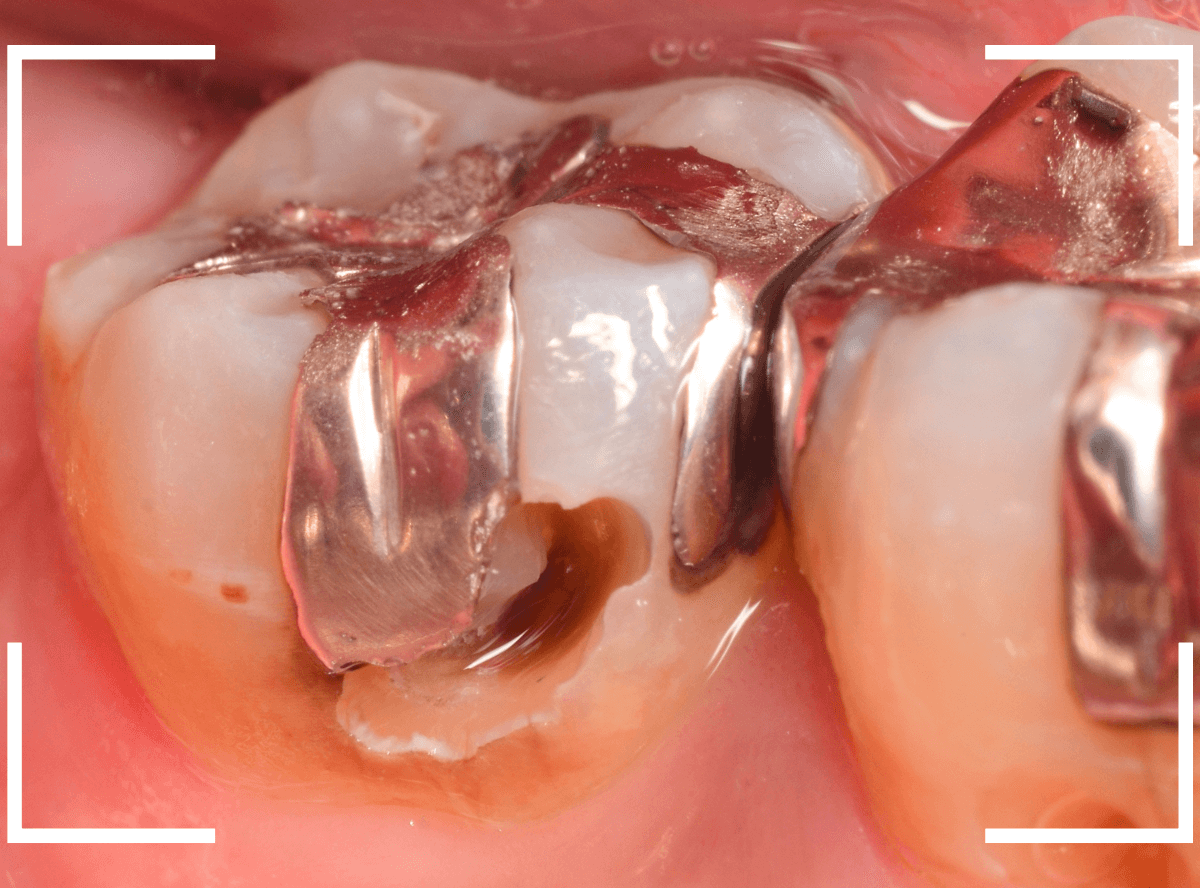

今回は、金属のつめものの下がレントゲン写真でわかりづらい虫歯になっていたケースです。

レントゲン写真で虫歯と思われる黒い影が明確でないために、金属の下がどうなっているのかがはっきりわかりません。

患者さんの自覚症状はありません。

患者さんに状況をお話して、金属を外して虫歯を確認し、治療をする動画です。

今後は、少しずつ動画も織り交ぜて、治療紹介していけたらなと考えています。